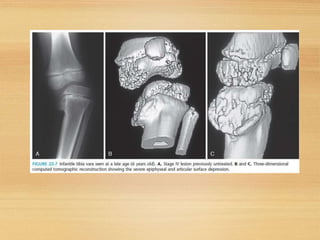

• Blount’s disease/ Mau-NilsonneSyndrome

Blount’s diseasedoes not require treatment to

improve. If the diseaseis caught early,treatment

with brace may be all that isneeded.

Bracing is not effective however withadolescents

with Blount’sdisease.

Untreated infantile Blount’s diseaseoruntreated

rickets results in progressive worsening of the

bowing in later childhood andadolescence.

Thetreatment of Blount diseasedependson

the ageof the child and the severity of the

varus deformity.